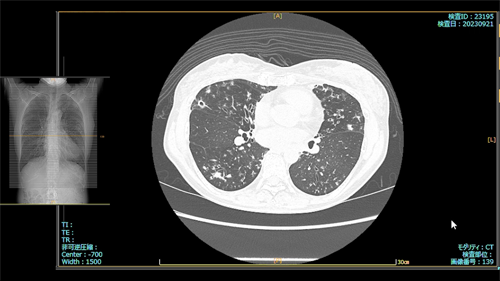

- 2023.09.21 入院加療の必要ありと診断された画像(国立系病院)